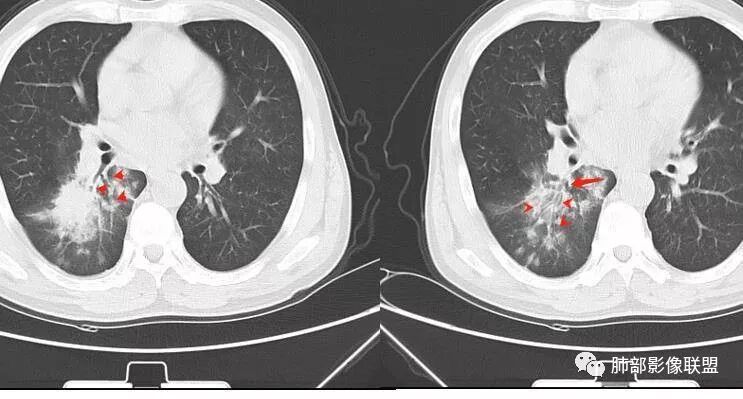

南边:这是下叶背段外侧的分支

病灶近端支气管通畅,局部体积缩小不明显,外围大内带小,沿支气管树蔓延过来

南边:紧贴着斜裂过来的一个病灶,它的特点是:外围大,内带小。它整个下叶背段体积与对侧相比稍微缩小一点,但是缩小地不是很厉害。外支朝前下走了,仔细看血管,肺动脉走行自然,直达远端。远端实变区是肉芽肿成分,稍微有一点低密度,没有明显坏死,稍微有一点点坏死。而且附近有很多卫星灶,附近很多斑片影,有一些明显有气道壁增厚,细支气管炎的特点,还有就是下叶其他段很多斑片状影。换个角度,第一如果是肺癌,刚才看到PET-CT提示肺癌伴阻塞性肺炎,这个是不符合的。第二如果是肺癌阻塞性肺炎,近端血管肺动脉走行不会那么自然集聚的,这个是不符合的。理由是:如果这个病灶是肺癌,那么明显属于中央型肺癌,中央型肺癌的特点是近端大,远端小,近端是一个肿块,远端阻塞,远端阻塞是阻塞性炎症或者不张,它应该体积缩小,斑片状实变,不会这么密实。刚才有老师提到支气管,这个片有缺陷的地方,给的图像好像那层,如果把其他图像拿开再重叠一下。

如果是单纯看这幅图像,会觉得背段外侧支气管分支堵塞的,但是看下面这层图

南边:你就发现外侧支气管朝下走的分支非常自然,通畅的。

南边:这个肺门区,11区和7区都有一些淋巴结,淋巴结的形态不是类圆形,而是梭形的。这个病灶给的图比较少,个人倾向,第一强化非常均匀,肉芽肿性病变;第二,里面血管走行非常自然,远端大近端小,倾向炎性,特别是下面还有斑片状影,非阻塞远端,支气管远端病灶下叶背段,其他段也有,所以我倾向炎性;另外,它里面整个走行符合支气管树爬行征,我倾向结核可能,首先我定在炎性,其次有没有结核的可能。